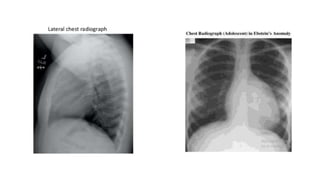

• The classic chest x-ray finding is a boot-shaped heart :

Boot-shaped heart

 CXR cardiomegaly – square shaped Lung – Oligaemic

 ECG- ‘p’ pulmonale ‘p’ mitrale, RBBB